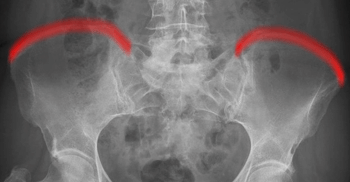

Becken a.p.

>90% aller Beckenringfrakturen lassen sich in der Übersichtsaufnahme, ggf. mit zusätzlicher Inlet und Outlet- Aufnahme (Bestimmung von Richtung und Ausmaß der Dislokation), diagnostizieren;

Beurteilungskriterien

- Symmetrie des Beckenskeletts, Position der Darmbeinkämme

- Weite und Symmetrie von Symphysenspalt (< 6mm) und ISF (< 4mm)

- Querfortsätze der unteren LWS, Kontur der Sakralforamina, ggf. CT

- Kontinuität der ilioischiadischen und iliopubischen Linie

- Azetabulumfraktur: vorderer und hinterer Pfannenrand, Pfannendachkontur, Köhlersche Tränenfigur, ggf. Zusatzaufnahmen (ap-Zielaufnahme, axiale, Ala- und Obturatoraufnahme), sowie CT

- Schenkelhalswinkel, Weite des Hüftgelenksspalt (4-5mm nach medial, 3-4mm nach kranial)

- Hüftluxation? Hüftkopf in der Beckenübersicht und in der axialen Aufnahme in der Pfanne zentriert?